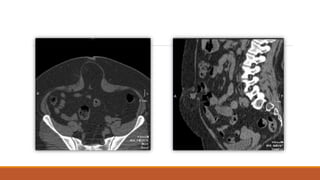

Pueden tomarse estudios de imagen (TAC, placa lateral de abdomen con contraste).

• USG o TAC (obesos).